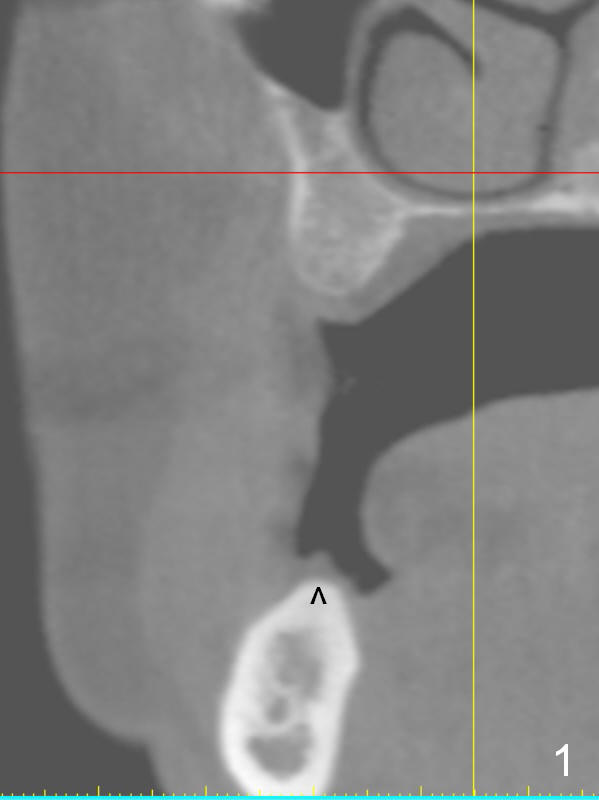

A 49-year-old lady is petit. An implant is placed at #3 and ready for restoration. The crest at #30 is narrow (Fig.1 ^). Bone density at the cortex, around the Inferior Alveolar Canal (IAC) and the medulla is D1, D2 and D3, respectively. It appears that a 10 mm bone-level implant is too close to IAC (Fig.2), whereas a 8 mm one has enough clearance (Fig.3,4). With the same diameter, there will be less thread exposure if the implant is placed a little lingually (Fig.4 (between arrows), as compared to Fig.3).